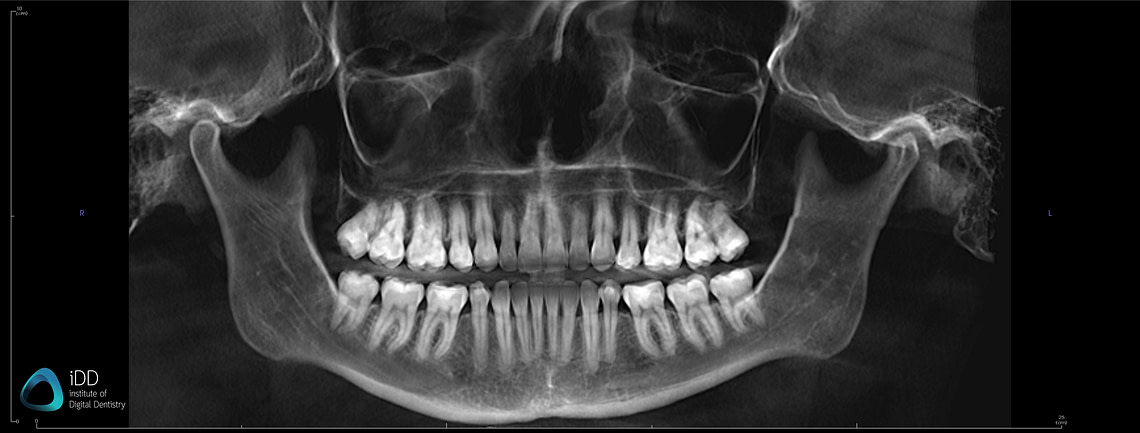

Panoramic image taken from a patient's CBCT.

These scans generate various file formats that carry a wealth of information, integral to dental diagnosis and treatment planning. In scenarios such as implant planning, endodontics, maxillofacial surgery, and orthodontics, traditional 2D images often fall short of providing the necessary depth of information. That's where CBCT comes in, filling the gap and enhancing diagnostic accuracy and precision.